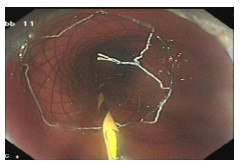

病例2,患者男,60岁。因“反复右上腹痛半月,加重2 d”于2022年8月29日来院急诊。入院查体:腹部膨隆,右上腹部压痛,无反跳痛。上腹部增强CT示结肠肝曲壁厚强化、管腔狭窄,考虑结肠肝曲恶性肿瘤并突破浆膜层,近段升结肠内容物堆积伴梗阻、肠壁肿胀伴扩张,病变周围及腹膜后多发淋巴结转移,肝多发转移。WBC12.7×109/L, N 81.1%。血CEA 29.05 ng/mL,CA19-9 39.07 IU/mL,CA125 41.21 U/mL。8月30日予行结肠镜下肠道支架置入术,检查进镜至结肠肝曲,见肠腔肿物堵塞,肠腔狭窄内镜无法通过,取病理活检后,沿导丝置入肠道非覆膜金属支架一枚(图 3)。患者肠道支架置入当天即感腹痛和腹胀症状消失,急性肠梗阻症状明显缓解。肠镜病理提示:结肠肝曲腺癌。经多学科讨论后于9月3日开始行XELOX方案术前转化治疗。目前患者病情平稳,规律行术前转化治疗中。

| 图 3 结肠肝曲癌伴肠腔狭窄行肠镜下结肠支架置入术 |